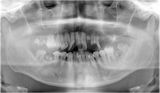

Q。虫歯や抜けたまま放置している歯がどの程度ありますか? ※本数/年収300万円以下/年収1000万円以上の順 1本以下 71% 84% 2、3本 15% 10% 4、5本 5% 4% 数えきれない 9% 2% また、生活習慣の差も影響する。 「低所得者の人のほうが安価でエネルギーを取れるような食事中心で、野菜が少なく糖質過多にりやすいことが言われています。ほかにも食事や睡眠の時間が毎日バラバラだったり、不規則な生活も虫歯になりやすい環境と言えます」 さらに、虫歯だけでなく歯並びにも収入による差が生じるという。世帯年収300万円と1000万円で「虫歯」にも格差。高額な歯科矯正を諦める親も | 日刊SPA!

年収と健康には因果関係がある――近年、さまざまな研究によってそんな事実から明らかにされてきた。格差が広がる日本でも問題視され始めた「健康格差」が今、新型コロナの影響で深刻化している。残酷なまでに広が…